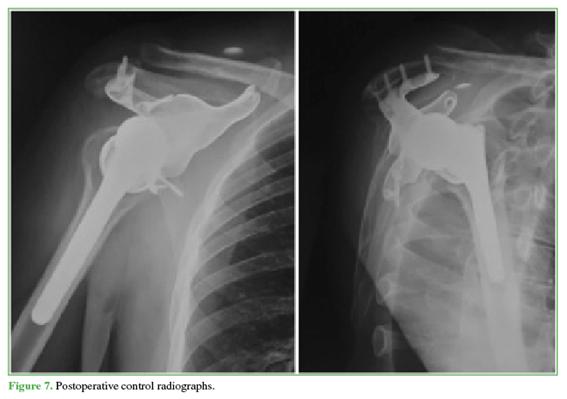

Using the cutting guides, the tumor was resected, and the 3D-printed implant was placed with acromial support to enhance fixation and component stability, counteract axial loads, and improve the function of the associated reverse prosthesis. The mass was resected with macroscopically negative margins; the deltoid was repaired with reinforced sutures, and implant stability was confirmed (Figure 6). Postoperative control radiographs were obtained (Figure 7).

Postoperative management included sling immobilization for approximately 4 weeks; pendulum exercises began in week 2, followed by passive/active-assisted stretching and progressive strengthening. At the 30-day follow-up, early range of motion was good; subsequent follow-ups were scheduled at 2, 4, 6, 12, and 48 months (Figure 8).